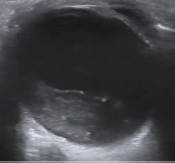

What’s the Diagnosis? Gepost op 26 oktober 201726 oktober 2017 door netwerkvsseh What’s the Diagnosis? @emdaily.cooperhealth.org Dit delen: Delen op X (Opent in een nieuw venster) X Share op Facebook (Opent in een nieuw venster) Facebook Delen op LinkedIn (Opent in een nieuw venster) LinkedIn E-mail een link naar een vriend (Opent in een nieuw venster) E-mail Afdrukken (Opent in een nieuw venster) Print Vind-ik-leuk Aan het laden... Gerelateerd